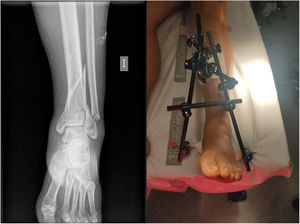

Of the total of 178 contusion patients, 107 fractures were recorded, of varying severity (60.1%), 3 of these open (2.8%): 2 open type II Gustilo and Anderson fractures of the third phalanx of the 3rd finger of the right hand, treated conservatively; an open type II fracture of the distal third of the left tibia requiring damage control surgery with closed reduction and external fixation (Fig. 3). The most frequent fractures were those related to segment 44 (distal tibia–fibula) according to the AO classification, with a total of 17 (15.9%); then 15 (14.1%) distal radius fractures; followed by segment 31 fractures (11.2%), with a total of 12, where the most frequent was the unstable pertrochanteric fracture (31-A21), with statistically significant differences (p<0.05).